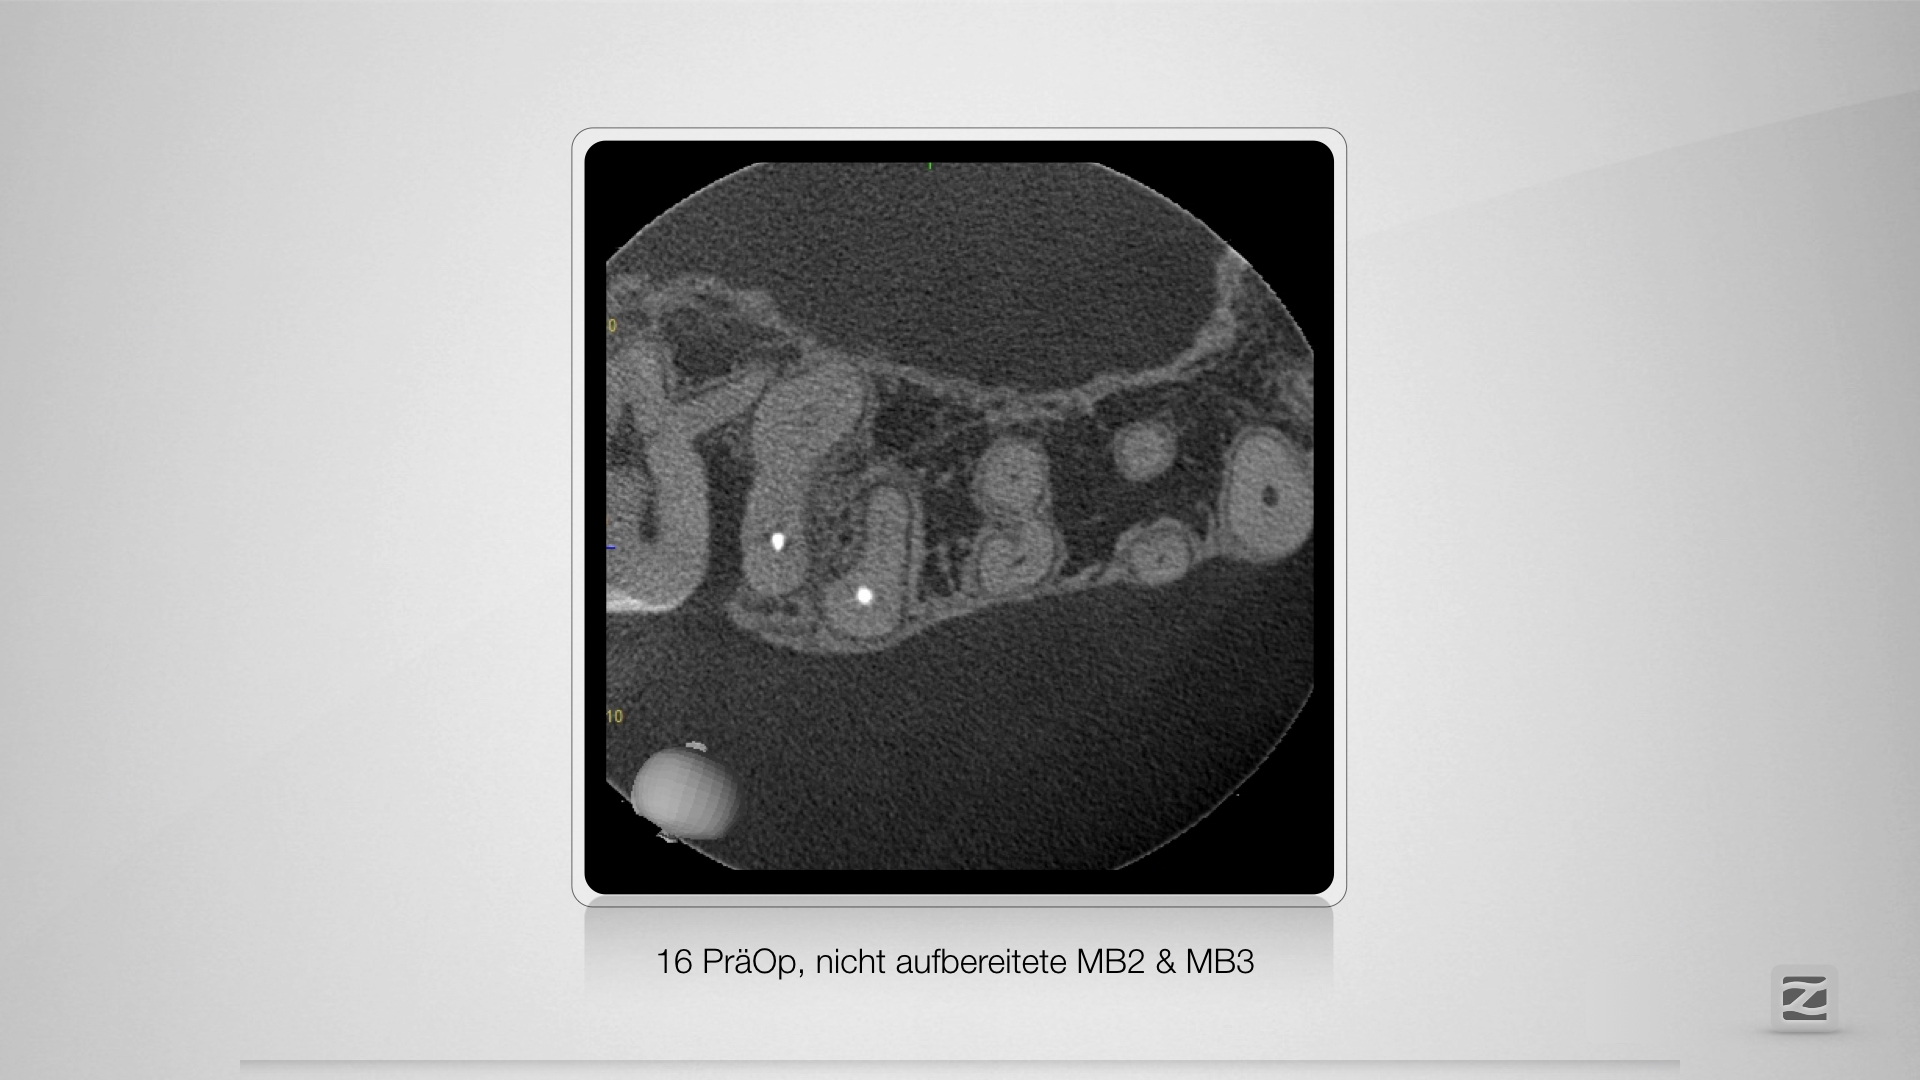

Selektive Revision